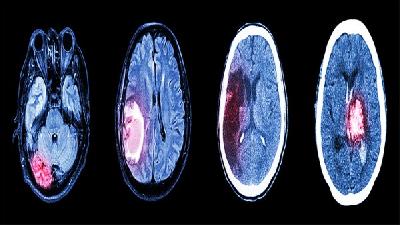

震颤型脑瘫多由锥体外系损伤及小脑损伤引起,其严重的影响着患者的身心健康,震颤型脑瘫是脑瘫常见类型之一,会导致震颤型脑瘫患者肌肉控制失调引起的身体运动困难和体位困难,严重的影响了患者的生活自理能力,所以震颤型脑瘫的治疗是非常有必要的。那么,男子震颤型脑瘫饮食方面需要注意什么呢?最近有越来越多的证据证实,饮食结构是震颤型脑瘫的一大重要因素。实验室研究结果显示,震...